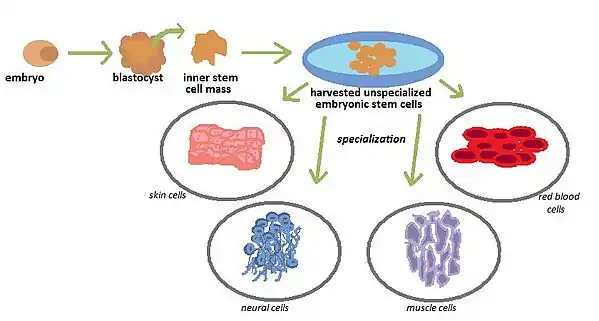

Embryonic Stem Cells

Embryonic stem cells are cells that are derived from embryos that have typically been harvested from eggs through in-vitro fertilization.[7] Embryonic stem cells are known as pluripotent, or having the ability to differentiate into every cell line within the organism. The embryos are 3–5 days old and consist of collections of hollow balls of cells that are called blastocysts.

In order to produce these blastocytsts, the embryonic stem cells must be harvested. The process of growing these stem cells is called cell culture, and is performed in the laboratory. The inner cell mass of human embryonic stem cells are placed onto a culture dish that has been coated with a medium that provides an adhesive surface to which the inner cell masses can stick. This medium is called a feeder layer, and is oftentimes composed of mouse skin cells. The human embryonic stem cells are then allowed to divide, spread, and attach to the medium of the culture dish in order to create a colony of embryonic stem cells. If the stem cell colony grows, divides and survives, the cells are plated onto new, clean culture dishes many times for the duration of many months in order to yield millions of embryonic stem cells, which is called a stem cell line. A sign that a stem cell line has developed successfully is if the cells have remained unspecialized for the duration of at least six months. If this is the case, the stem cell line can then be used for further testing and experimentation.

Specialization

The purpose of harvesting embryonic stem cells is to create a colony of self replicating cells that have the potential to specialize into specific cells of interest that can be used to treat diseases.While they are being grown, the cells remain unspecialized but once they are allowed to clump together under certain specific conditions, they begin to form various specialized cells and tissues. The challenge scientists are currently facing is figuring out how to control the specialization to create specific cells of interest as opposed to spontaneous specialization that can result in the formation of various cells that carry unwanted specific functions. One such way to control specialization is by subjecting the colonies of embryonic stem cells to changes in chemical composition within the culture medium, changing the surface of the culture dish, or inserting specific genes into the culture to change the composition of the harvested cells. By transplanting the successfully specialized embryonic stem cells into humans, scientists can formulate treatments for certain diseases such as Parkinson’s Disease, diabetes, spinal cord injury, heart disease as well as vision and hearing loss.